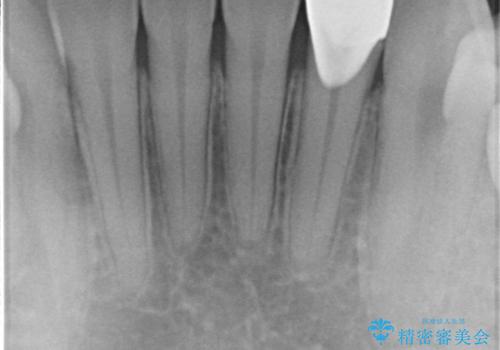

矯正治療前のかみ合わせのせいでかなり削れてしまっていたようです。その場合、矯正治療後に修復するのがおすすめです。

また、クラウンに修復するメリットとして、そのまま使っていると欠けているせいで薄い歯質がうすくなり、さらに割れてしまうリスクを防止することができます。